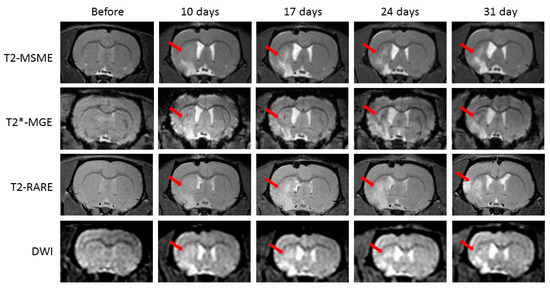

2.2. Injections of Both AAV-pDCX-FerrH and AAV-pDCX-eGFP Cause Signal Hypointensity on T2*-MGE Images in the Sham-Operated and Post-Ischemic Animals

2.3. T2* Signal Hypointensity Correlates with FerrH and eGFP Accumulation

- Results of our study showed that rat brain could be successfully infected with AAV-pDCX-FerrH and AAV-pDCX-eGFP viral vectors for expression of either ferritin or eGFP. Both vectors caused at about 20% decrease in signal hypointensity in the areas near the SVZ on T2*-weighted MRI at one month after intracranial injection of the viral constructs.

- The location of the signal hypointensity areas coincides with zones of ferritin and eGFP accumulation in immunohistochemical slides and zones of iron accumulation in Prussian blue staining a month after viral injection. RT-PCR data confirmed upregulated expression of the ferritin in the corpus callosum and caudoputamen in the left hemisphere of the rat brain on day 7 after intracerebral injected of the adenoviral vector construct.